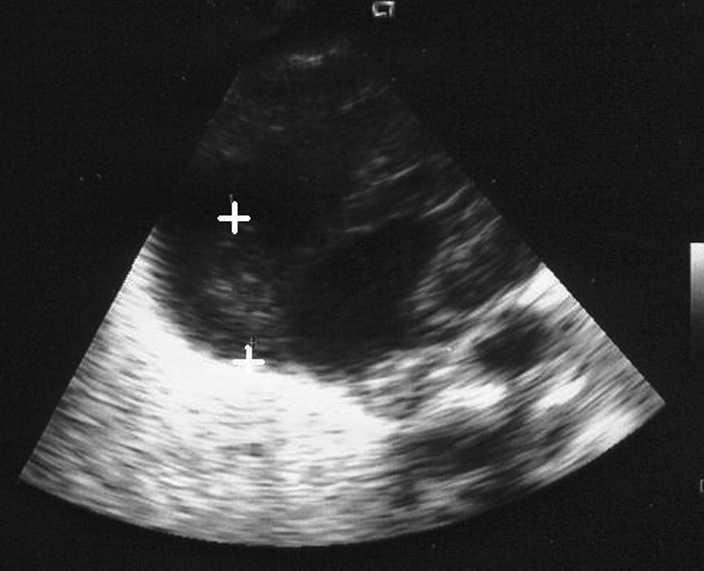

Se trata de un varón fruto de segunda gestación de 26 semanas que cursó con sospecha de tuberculosis miliar tratada con rifampicina, isoniacida y etambutol desde una semana antes del parto. La madre tuvo un aborto previo en el primer trimestre. Se aisló Ureaplasma urealyticum en el cultivo de secreciones vaginales. El niño no presenta maduración pulmonar y el parto fue eutócico. El test de Apgar al minuto fue 5; a los 5 min, 7, y a los 10 min, 8. Fue sometido a reanimación tipo IV (intubación orotraqueal y ventilación con bolsa y mascarilla). Peso al nacer: 810 g. A su ingreso se administra agente tensiactivo pulmonar exógeno (poractán) y se aprecia radiológicamente patrón de enfermedad de membrana hialina, por lo que se administra una segunda dosis de agente tensiactivo a las 6 h. A las 48 h de vida se realiza ecografía craneal en la que se aprecia hemorragia intraventricular de grado II. En controles posteriores se observa que evoluciona a leucomalacia periventricular con dilatación ventricular. A los 20 días de vida se ausculta soplo sistólico 2/6 máximo en borde esternal izquierdo, se palpa hepatomegalia y se distingue analíticamente trombocitopenia. Se realiza ecocardiografía en la que se aprecia trombo en aurícula derecha en la entrada de vena cava localizado en la punta de catéter epicutáneo (fig. 1). Ante el alto riesgo de la trombectomía quirúrgica por su bajo peso y el riesgo de la trombólisis en dosis sistémica, dado el antecedente de hemorragia intraventricular, se inicia tratamiento, a través del epicutáneo cuya punta se encuentra en el trombo, con urocinasa en dosis bajas (2.000 U/kg/h) y se comprueba ecocardiográficamente la desaparición del trombo tras 14 días de fibrinólisis. Se mantiene en tratamiento con heparina de bajo peso molecular (1 mg/kg/12 h) durante 6 semanas y se da de alta en buen estado a los 3 meses de su nacimiento.

Figura 1. Trombo en aurícula derecha.